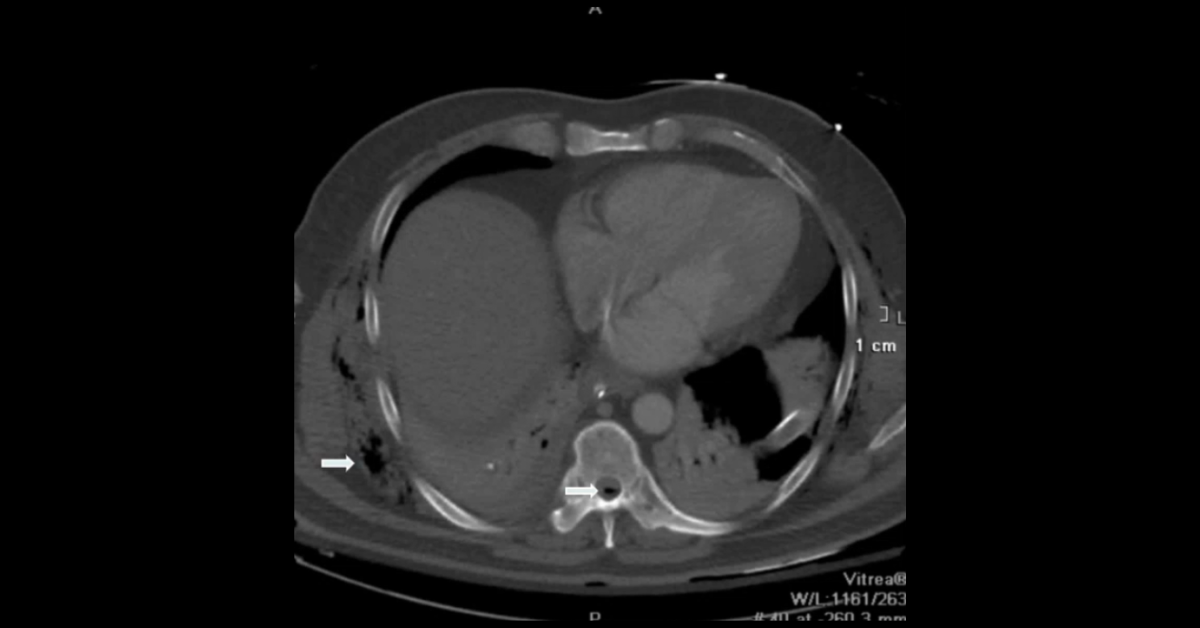

Presented by Vincent Mellnick, MD at Practical Radiology 2025. The upper gastrointestinal tract can be oft-overlooked site of disease in the emergency department patient, but is frequently be the site of pathology, including inflammation/infection, ischemia, obstruction, perforation, and hemorrhage. This talk will discuss common (and some uncommon) conditions causing these presentations in the esophagus, stomach, and duodenum, with emphasis on CT findings.